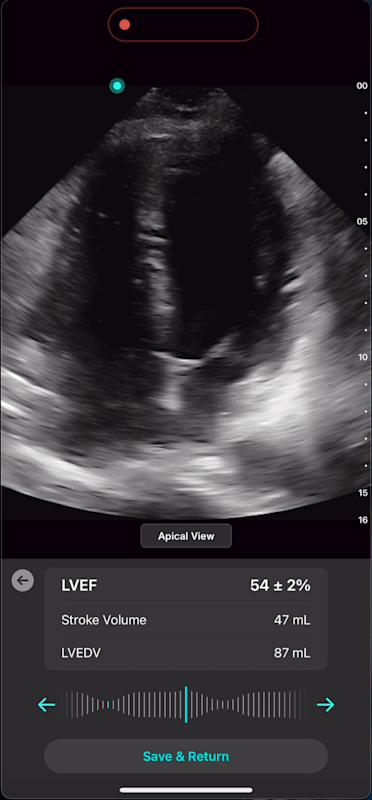

With Exo’s Cardiac AI, you can measure left ventricular ejection fraction (LVEF) and stroke volume in a few heartbeats in both parasternal long axis (PLAX) and apical four-chamber (A4C) views, making it easier than ever for POCUS users to get to answers.